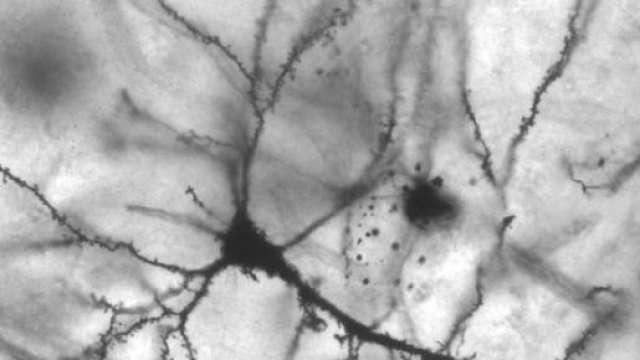

Passo avanti per la ricerca italiana: uno studio condotto da un team di scienziati dell'Università di Trento potrebbe rivelarsi la svolta per la cura delle malattie neurodegenerative come il morbo di Parkinson, l'Alzheimer o la SLA (Sclerosi Laterale Amiotrofica). Tale studio infatti ha permesso di rilevare un 'interruttore' molecolare che, per usare una metafora, potrebbe 'spegnere' i sintomi delle malattie neurodegenerative. I risvolti rivoluzionari di tale ricerca, pubblicata dalla rivista scientifica 'Neuron', sono stati presentati al Convegno annuale dei ricercatori di Telethon di Riva del Garda, tenutosi quest'anno dal 9 all'11 marzo.

La biologa Maria Pennuto, esperta del Centre for Integrative Biology (CIBIO) dell'Università di Trento e coordinatrice dello studio, spiega che l'atrofia muscolare spinale bulbare è causata da un'alterazione del recettore per gli ormoni androgeni, una proteina situata sia nei testicoli che nei neuroni che comandano il movimento e nei muscoli. Nello studio viene spiegato che l'enzima PRMT6 (protein arginine methyltransferase 6) attiva il recettore mutato più di quello normale: i ricercatori sono riusciti ad identificare proprio il punto preciso in cui le due molecole interagiscono, cioè il meccanismo attraverso cui l'enzima PRMT6 attiva il recettore e il sito in cui lo modifica. Si è giunti quindi alla dimostrazione che, spegnendo questo interruttore molecolare, si può ottenere l'attenuazione dei sintomi della malattia.